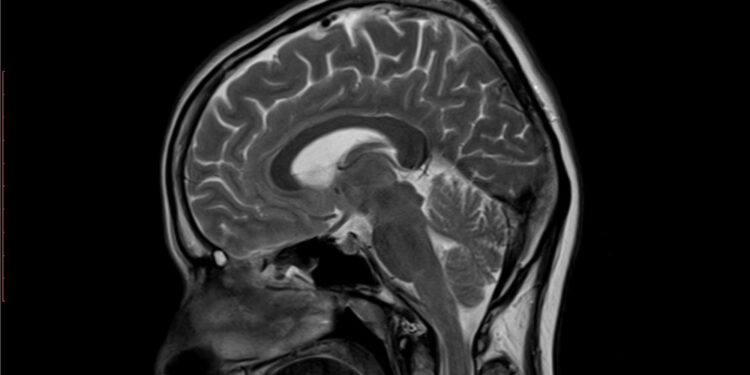

Pastebėjus kūdikyje galimus raidos ar neurologinius sutrikimus, gydytojas dažniausiai skiria tyrimus, kurie leidžia detaliau įvertinti smegenų struktūrą. Tuo tikslu atliekami ultragarsiniai, kompiuterinės tomografijos (KT) arba magnetinio rezonanso tyrimai (MRT). Tyrimų metu įvertinamas išorinės smegenų dalies lygumas ir griovelių storis.

Lissencefalijos sunkumas gali būti apibūdintas keliais lygiais. Pavyzdžiui, kai beveik visose smegenų dalyse nustatomas paviršiaus glotnumas (agyrija), kalbama apie pirmą sunkumo laipsnį. Tai labai retas atvejis, paprastai reiškiantis itin sudėtingą eigą ir stiprius raidos vėlavimus.

Daugumai vaikų būdingas trečias lissencefalijos laipsnis – tuomet priekinėse ar šoninėse smegenų dalyse matomas griovelių sustorėjimas (pachygyrija), o kitose vietose – paviršiaus lygumas.